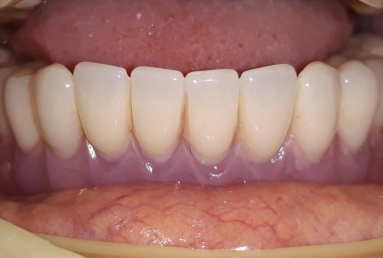

The mobile prosthesis is fixed with 4 locators that firmly stabilise it. The mastication, talking and aesthetics is very comfortably and safely obtained.

After finishing the lower arch, we did the same steps for the upper arch. The mobile full maxilary prosthesis is sustained by 4 dental implants and 4 locators.